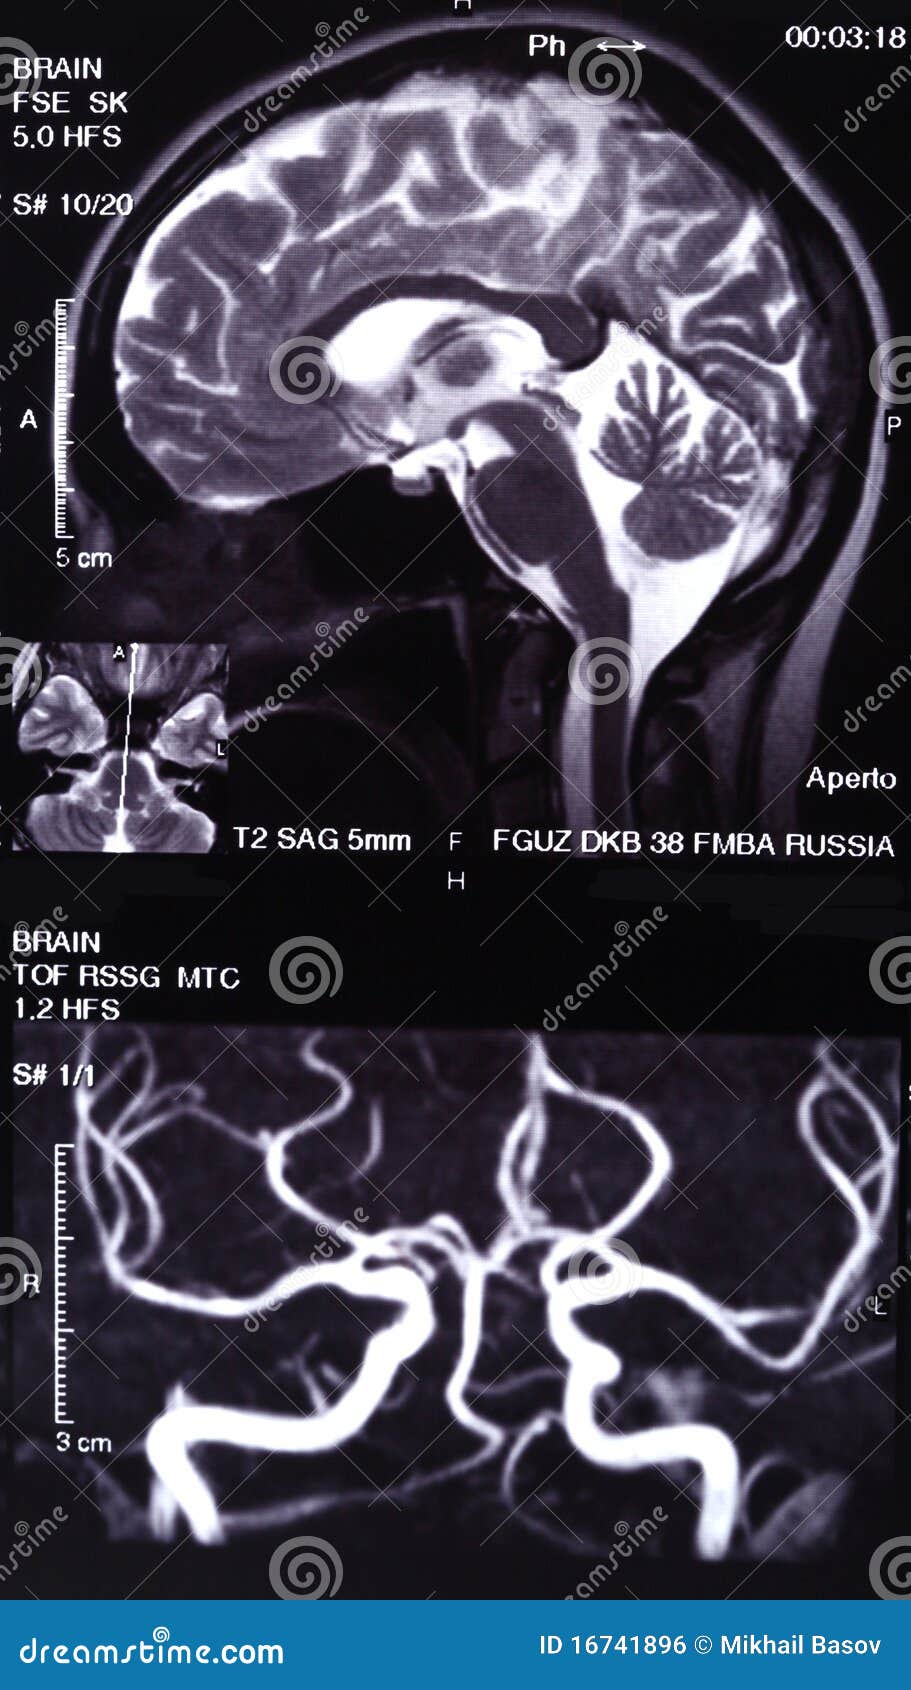

From www.dreamstime.com

MRI and MR angiography stock photo. Image of imaging 16741896 What Is A Mri Angiography In magnetic resonance angiography (mra), a powerful magnetic field, radio frequency waves and a computer are used to evaluate blood. Magnetic resonance angiography (mra) is an imaging test that shows your blood vessels and blood flow. An mra can detect narrowing or. A regular angiogram requires inserting a thin tube. It looks just at the body’s blood vessels. Magnetic resonance. What Is A Mri Angiography.